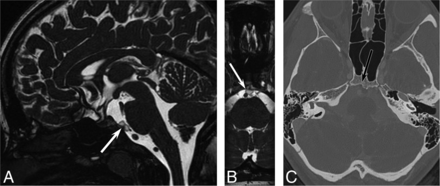

The patient returned 4 years later with recurrent headaches and again underwent MR imaging (Fig 2). The lesion had marginally enlarged but retained all of its benign features. Because of the change in size, the neurosurgery team advised resection, and the patient agreed. The resection was accomplished with an endoscopic endonasal transclival resection.4 Histopathologic analysis (Fig 3) revealed a neoplasm composed of cells with multivacuolated (physaliphorous)-to-eosinophilic cytoplasm embedded in a myxoid background, with a chronic lymphocytic inflammatory infiltrate seen in fibrous septa separating the lobules of the tumor. There was a variable degree of nuclear enlargement, hyperchromasia, and nuclear membrane irregularities. Mitotic activity was sparse, and the Ki-67 proliferation index was very low (<1%), indicating indolent or benign disease. However, no amplification of 1p36 or 9p21 was detected with fluorescence in site hybridization, so the tumor could not be classified as having minimal risk. Lobules of the tumor were identified intradurally as well as extending into the clivus, indicating some degree of aggressive features. Immunohistochemical staining for Brachyury showed strong, diffuse nuclear staining, confirming notochordal origin. When all of the histopathologic, genetic, and fluorescence stain data were taken into consideration, a diagnosis of low-grade chordoma was made, with a description of the relatively bland histologic features displayed by the tumor. Follow-up MR imaging 6 months later revealed no evidence of residual disease.

Follow-up imaging 4 years later. Axial steady-state free precession MR imaging (A) shows increased lesion size (arrow) with new involvement of the clivus. Sagittal reformat (B) shows increased superoinferior extent. The clival involvement is confirmed on axial contrast-enhanced CT (C).